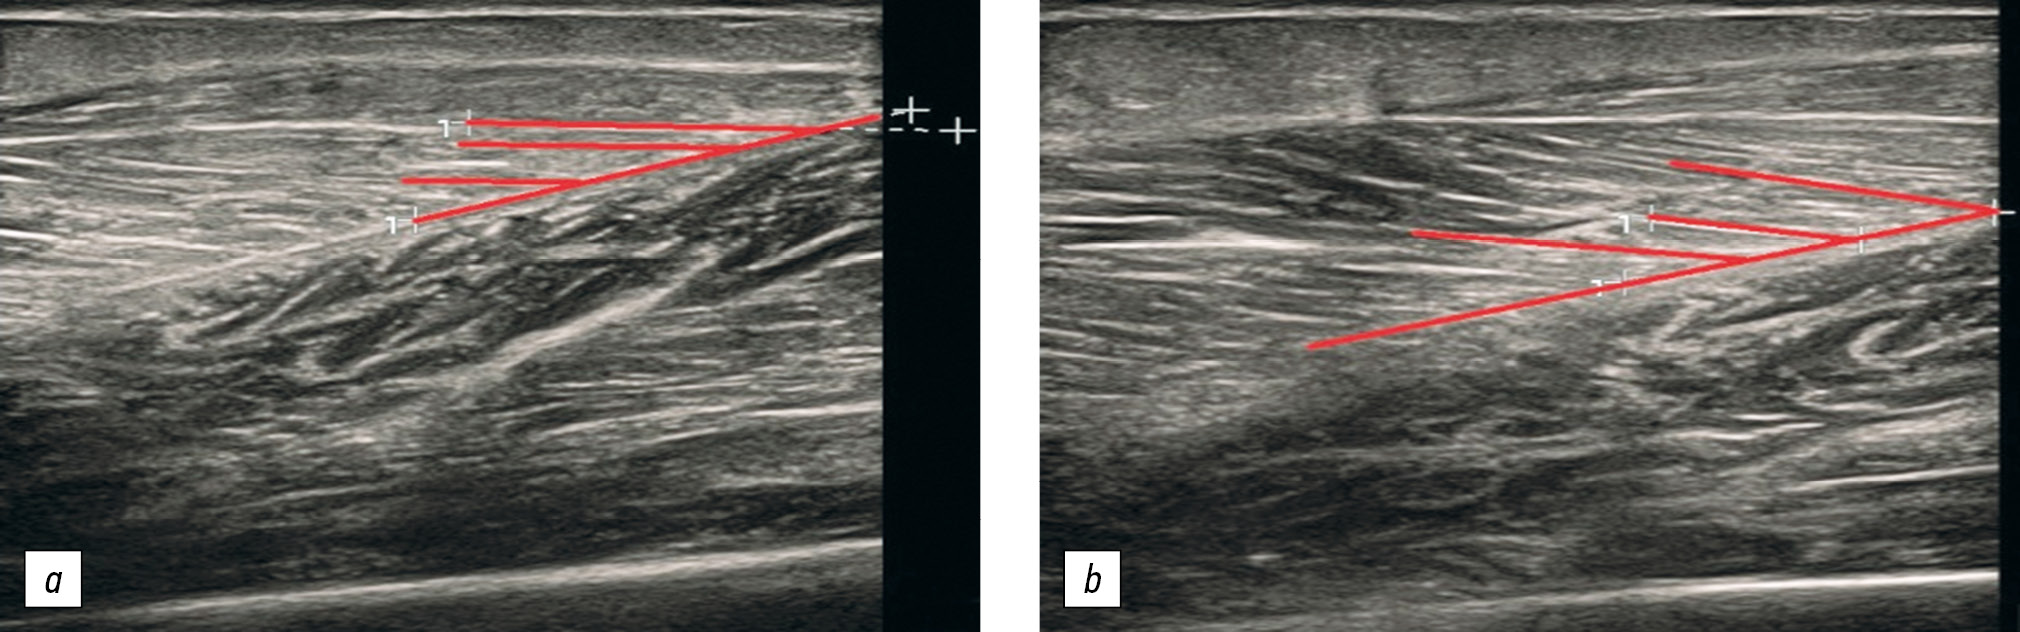

Как следует из в табл. 2 и 3, УП медиальной головки икроножной мышцы и камбаловидной мышцы продемонстрировал достоверное увеличение, тогда как для латеральной головки икроножной мышцы данный показатель статистически значимо не изменился. На рисунке представлены ультрасонограммы медиальной головки икроножной мышцы пациента с ГПУАС до начала программы стретчинга и через 6 мес. ее регулярного применения.

Рисунок. Ультрасонограммы медиальной головки икроножной мышцы пациента с гипермобильным плоскостопием и укорочением ахиллова сухожилия — увеличение угла пеннации: а — до начала программы стретчинга; б — через 6 мес. ее регулярного применения